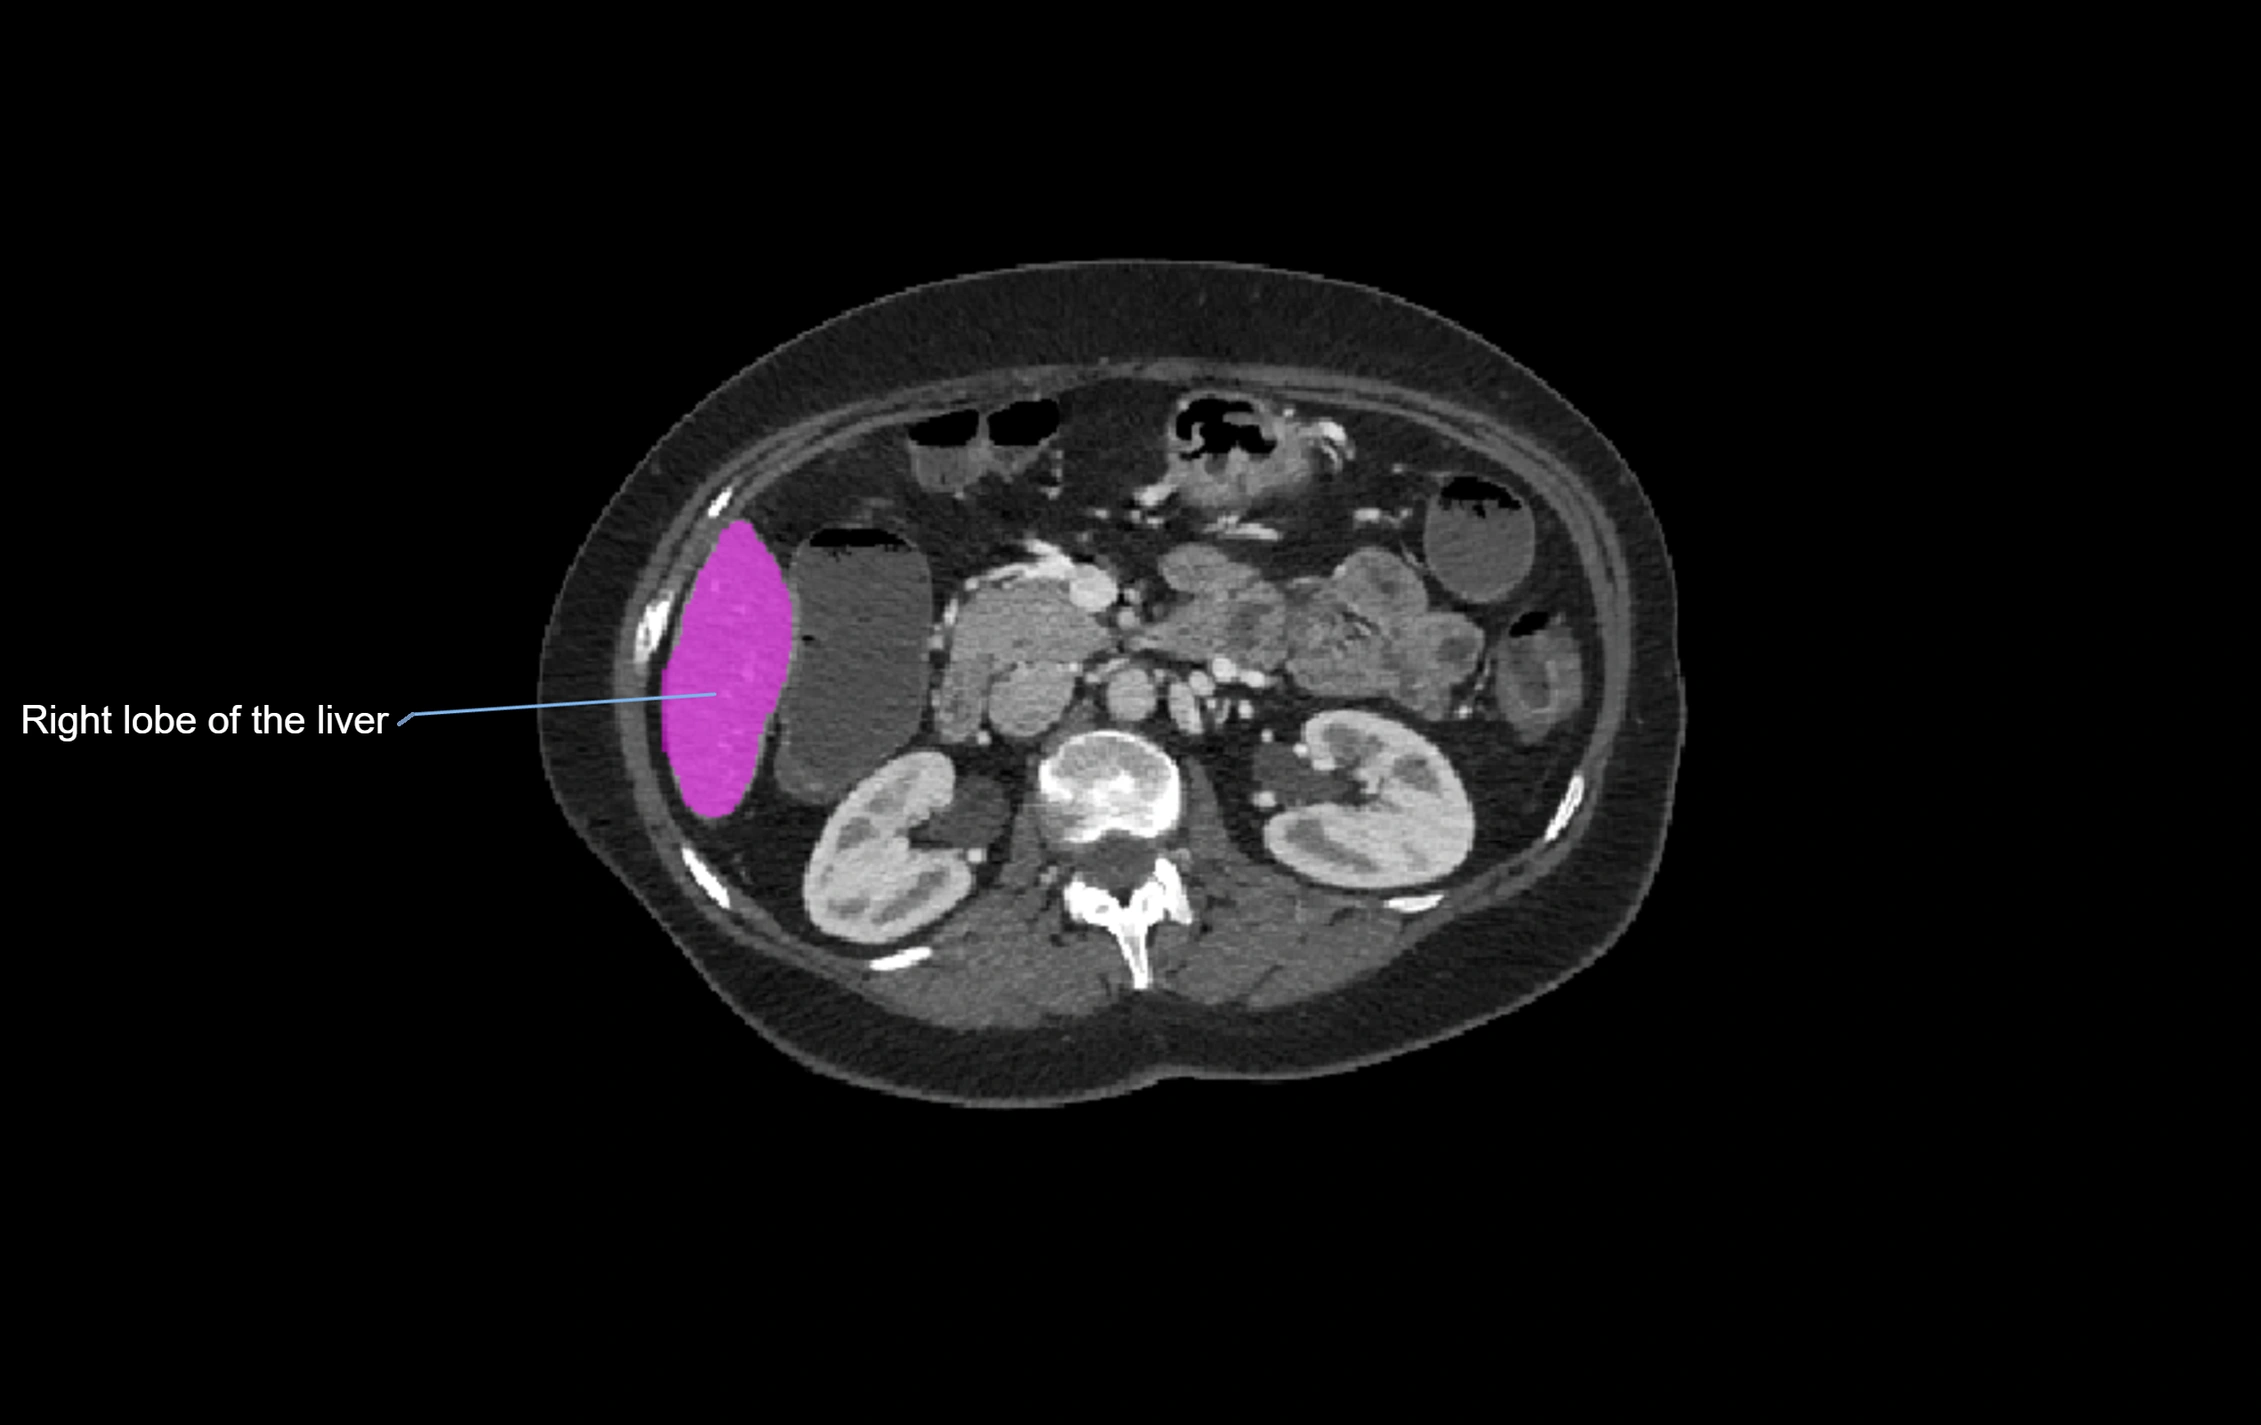

CT Appearance

CT Pre-Contrast:

• Caudate lobe appears as a soft-tissue density, isodense to the rest of the liver

• Enlargement may be appreciated in cirrhosis or Budd–Chiari syndrome

CT Post-Contrast:

• Homogeneous enhancement in the portal venous phase, similar to rest of liver

• Independent venous drainage into the IVC may be visualized

• Lesions follow characteristic CT enhancement patterns (HCC: arterial hyperenhancement with washout; hemangiomas: peripheral nodular enhancement with centripetal fill-in)

CT Venous Phase (functional significance):

• Caudate lobe often enhances relatively more than other lobes in Budd–Chiari syndrome, due to preserved venous outflow